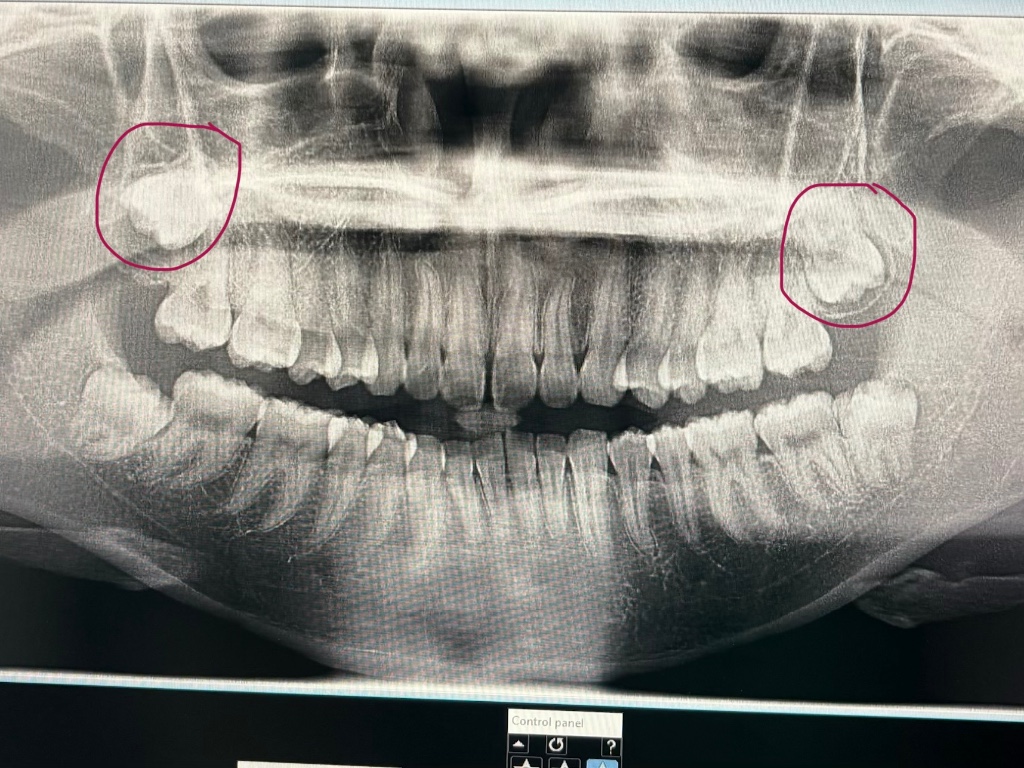

อยากจะสอบถามเรื่องฟันคุดค่ะ 🦷😈

พอดีกำลังจะจัดฟันค่ะ คุณหมอแนะนำให้ผ่าฟันคุดด้านล่าง 2 ซี่ (ซ้าย 1 ขวา 1)

แต่พอดูฟิล์ม X-ray แล้ว สังเกตว่าฟันกรามด้านบนทั้ง 2 ข้าง เหมือนจะเป็นฟันคุดด้วย (หรือเปล่าไม่แน่ใจ) (ยังไม่เคยมีอาการปวดหรืออักเสบเลยค่ะ) เลยสงสัยว่า

1.จากภาพลักษณะนี้ ถ้าเป็นฟันคุด ด้านบนจำเป็นต้องผ่าออกด้วยไหมคะ

2. ฃหรือถ้ายังไม่มีอาการ สามารถเก็บไว้ได้ ไม่ต้องผ่าเลยก็ได้